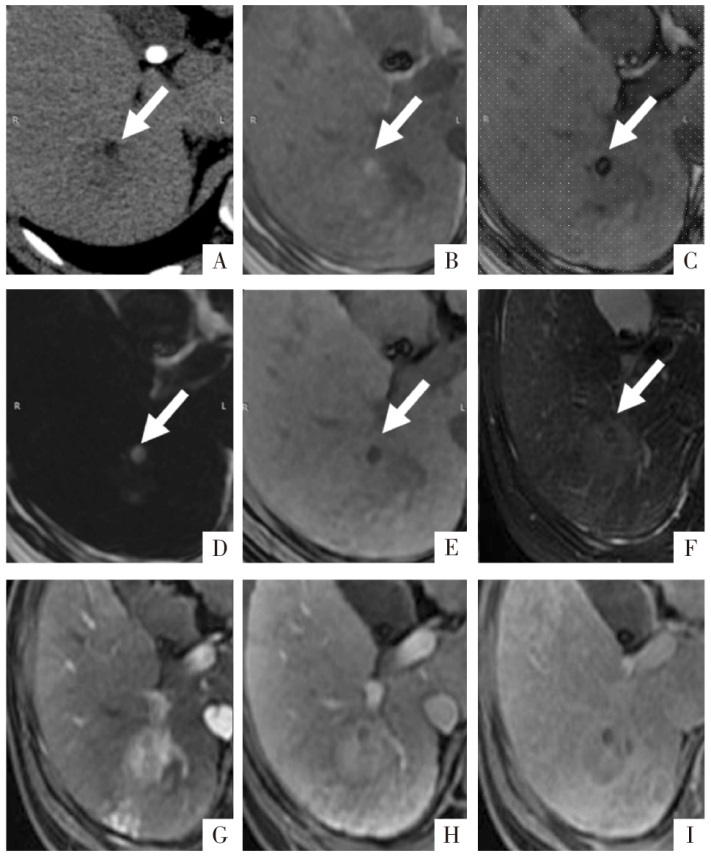

图5

病人男,41岁,肝细胞癌。A图,CT影像显示低密度病灶内极低密度区(白箭),测量CT值为-48 HU。B—E分别为T

1

WI同相位、反相位、脂像和水像,同相位为高信号,反相位可见高信号核心及勾边,形似小脂肪块。F图为T

2

WI,显示肿块呈轻中度稍高信号;G、H、I图分别为动脉期、门静脉期及延迟期影像,可见非周边的动脉期高强化、延迟期廓清以及强化包膜征象,以上为肝细胞癌典型征象。